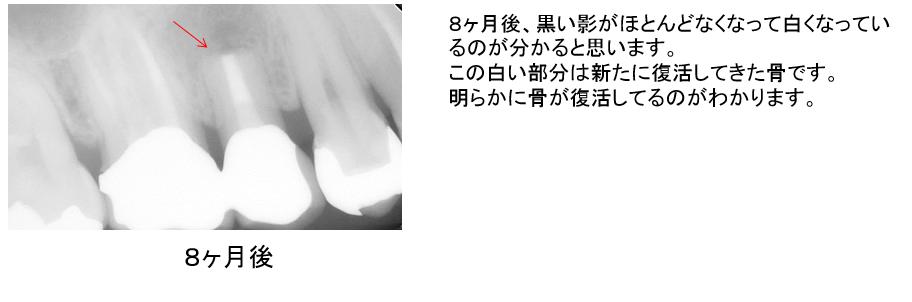

歯根端切除術後です。

根の先端が短くなっているのが分かると思います。